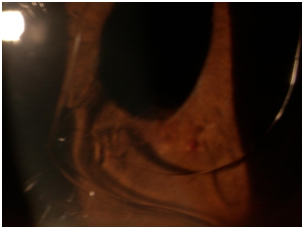

Patient presented in urgent care reporting that the condition is not any better with complaints of pain, redness, photophobia, tearing, discharge, discomfort, and shortness of breath. Patient reported good compliance on taking prednisolone, Combigan®, Azopt®, but has not obtained atropine from the pharmacy yet. Patients VA was light perception OD and similar entrance testing results as the last follow up. Slit lamp examination revealed microcystic corneal edema, diffuse 3+ PEE, the same anterior chamber findings, except newly noted that the lens OD was a poorly fitting ACIOL touching the cornea and the iris. Intraocular pressures were 47 mmHg, 14 mmHg OD, OS. After dilation, the 2+ vitreous hemorrhage was noted again and all other findings appeared normal (Figures 1−3). Additional diagnostic testing was ordered for exterior/slit lamp photos, which were interpreted as a poorly fitting ACIOL OD with hyphema and NVI. The retinal surgeon performed an intravitreal injection of Avastin® 1.25 mg to regress neovascularization of the iris and to stabilize/improve the eye. Post-injection IOP via tactile measurements were now estimated to be 21 mmHg, 21 mmHg OD, OS. After the injection, the assessment of proliferative diabetic retinopathy with UGH syndrome OD was made. The plan stated to proceed with glaucoma/cataract specialist with ACIOL removal and IOP management.

Figure 1 16x Slit lamp photo of NVI growing over the pupillary ruff.

Figure 2 10x Slit lamp photo of malpositioned ACIOL with haptic rubbing on iris tissue causing hyphema.

Figure 3 16x Slit lamp photo of hyphema with fresh blood inferiorly.